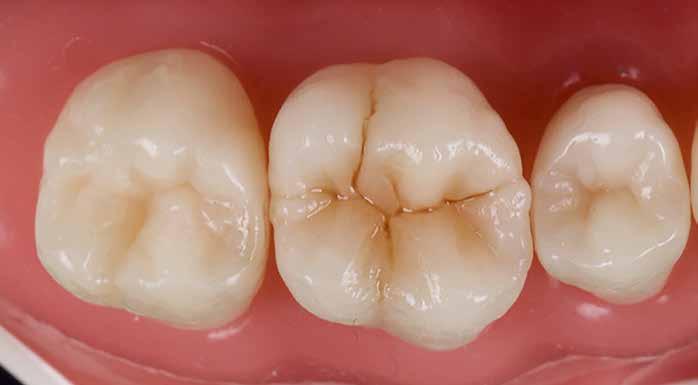

A posterior fogak direkt kompozit restaurációja az egyik leggyakrabban végzett beavatkozás a fogászatban. Az elmúlt években kiemelt figyelem irányult az elérhető eredmények optimalizálására, különös tekintettel a II. osztályú kavitás dobozának (Class II box) kialakítására, és a polimerizációs zsugorodásból eredő feszültség kezelésére. A téma körüli széles körű szakmai diskurzus ellenére van egy olyan lépés, amely gyakran nem kapja meg a kellő figyelmet: a mechanikai formázás protokollja. A mechanikai formázás alatt a restauráció kontúrjának kialakítását, a felesleges kompozit eltávolítását értjük a marginális szélekről, illetve ide tartozik a végső polírozás is. Ez a folyamat három fő lépésre bontható: a felszín oxigén által gátolt, nem polimerizált rétegének eltávolítása, a durva finírozás és a végső polírozás. Jelen publikációban részletesen bemutatjuk ezeket a lépéseket, valamint egy klinikailag hatékony megközelítést vázolunk fel a direkt posterior kompozit restaurációk befejezésére.

6. ábra: I. osztályú restaurációk az első moláris és a második premoláris fogakban. A széleken felesleges kompozit figyelhető meg (piros nyilak jelölik).

Klinikai példa az alábbi képen látható:

2. ábra: A páciens egy nem megfelelő I. osztályú ezüstamalgám töméssel és II. osztályú szuvasodással jelentkezett. A fog izolálása kofferdám alkalmazásával történt.

3. ábra: A preparálás, a bondozás és a kompozit felvitele után. (Megjegyzés: némi kompozit túlfolyás látható a mesiális doboz axiális falain).

4. ábra: A durva finírozás után a restauráció pereme sima és anatómiailag is megfelelő.